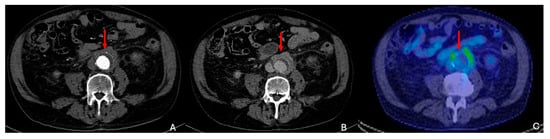

8.1. Infected Aneurysm

- Manta, R.; Lauri, C.; Taurino, M.; Signore, A. Imaging of Vascular Graft/Endograft Infection with Radiolabeled White Blood Cell Scan and [18F]FDG PET/CT. Hemato 2023, 4, 285–300. [Google Scholar] [CrossRef]

| Infected | In the context of systemic infection, more common in immunocompromised patients | Secondary to bacterial infection | - Fever - Abdominal pain - Elevated inflammatory markers - Risk of rapid expansion and rupture | Saccular aneurysm with periaortic gas, inflammatory signs 18FDG PET: Increased uptake in infected areas |